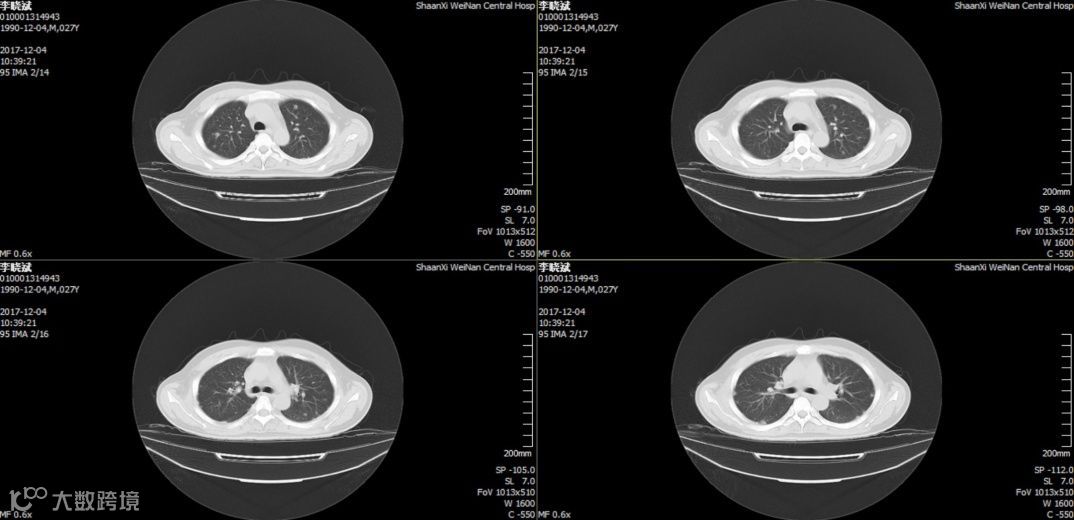

2018.11.25复查CT:双肺炎症,考虑特殊细菌感染可能,双侧胸膜腔少量积液,心包少量积液,腹腔少量积液,少许游离气体,部分包裹,肝右叶、脾实质混杂密度包块,脓肿并气体。因经济原因换用头孢曲松 2.0 g,QD,ivgtt。12月8日再次发热,12月12日肝脏穿刺引流后体温逐渐正常,CT提示病灶逐渐吸收。